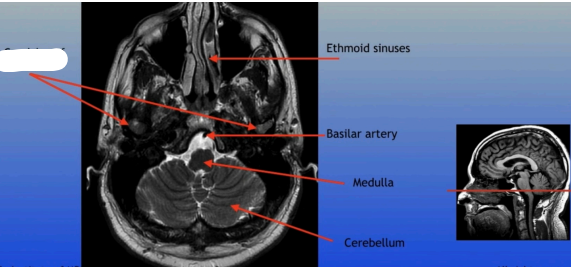

Condyles of the TMJ

Ethmoid Sinuses

Basilar Artery

Medulla

Cerebellum